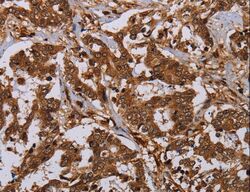

Supportive validation

- Submitted by

- LSBio (provider)

- Enhanced method

- Genetic validation

- Main image

- Experimental details

- Immunohistochemistry of paraffin-embedded Human liver cancer using MOB1A Polyclonal Antibody at dilution of 1:30.